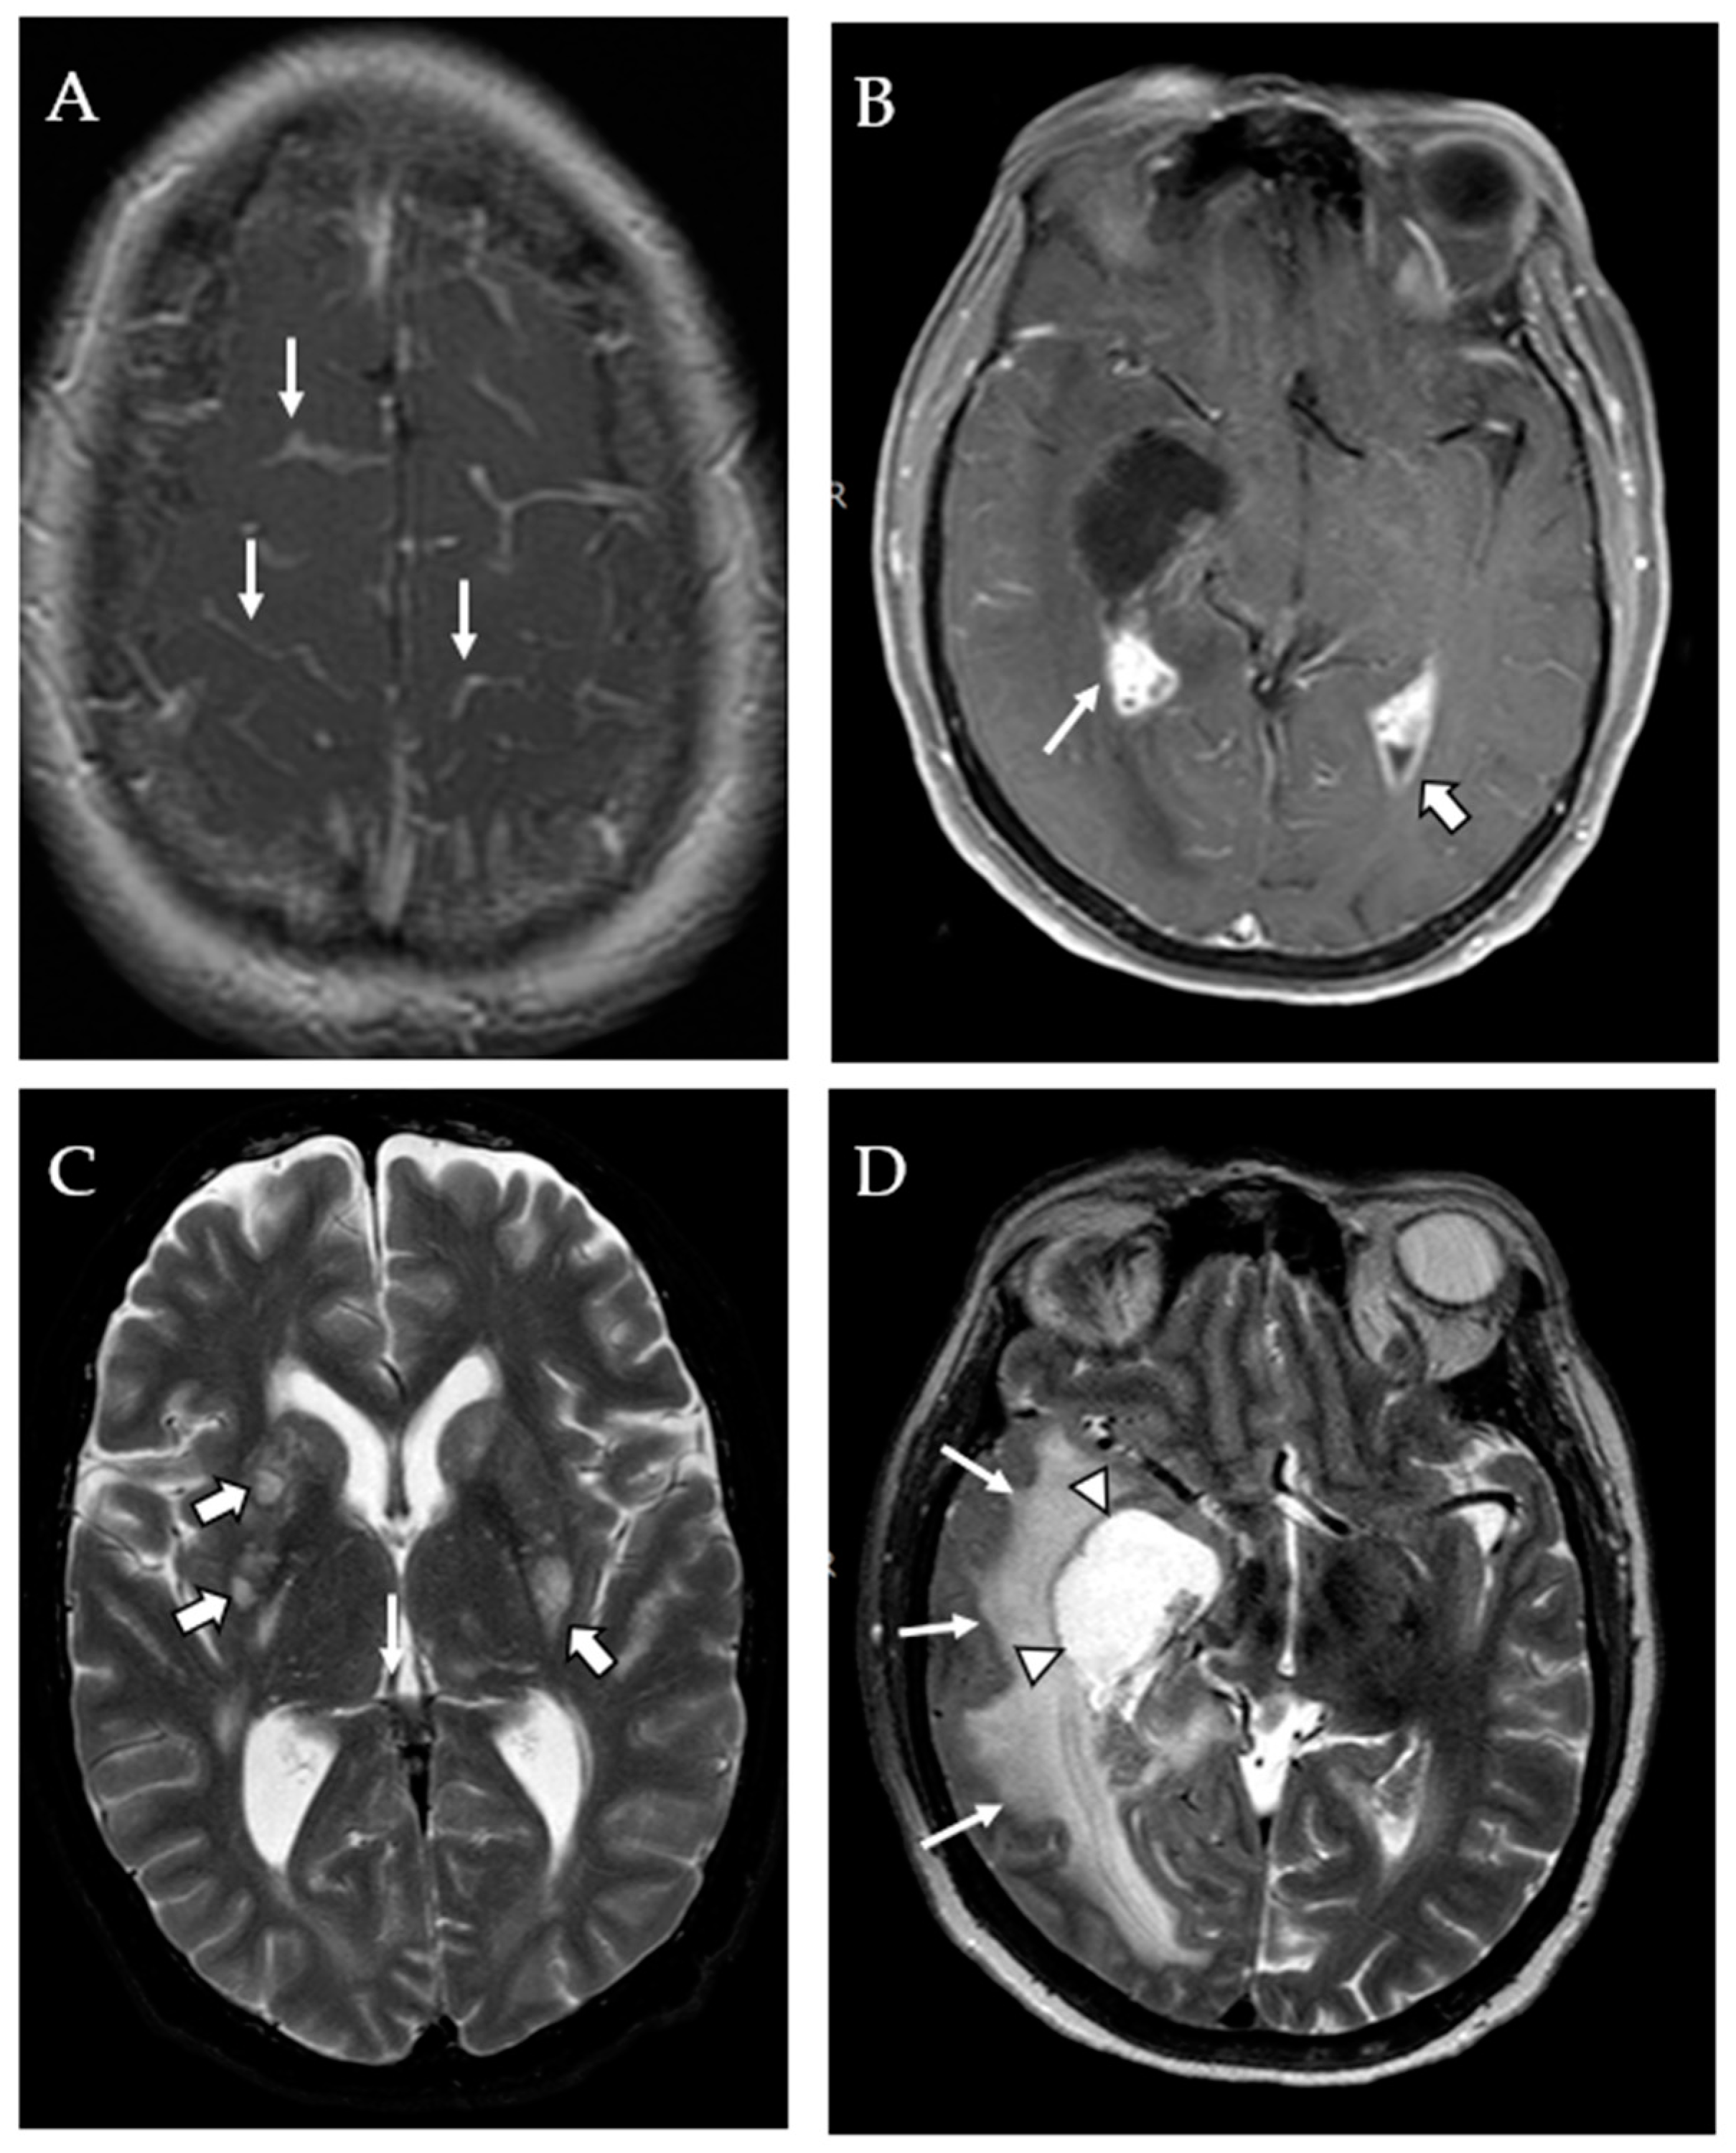

3.2. MRI Findings

4.1. Mass Lesions and Dilated VR Spaces

4.2. Infarcts and Atrophy